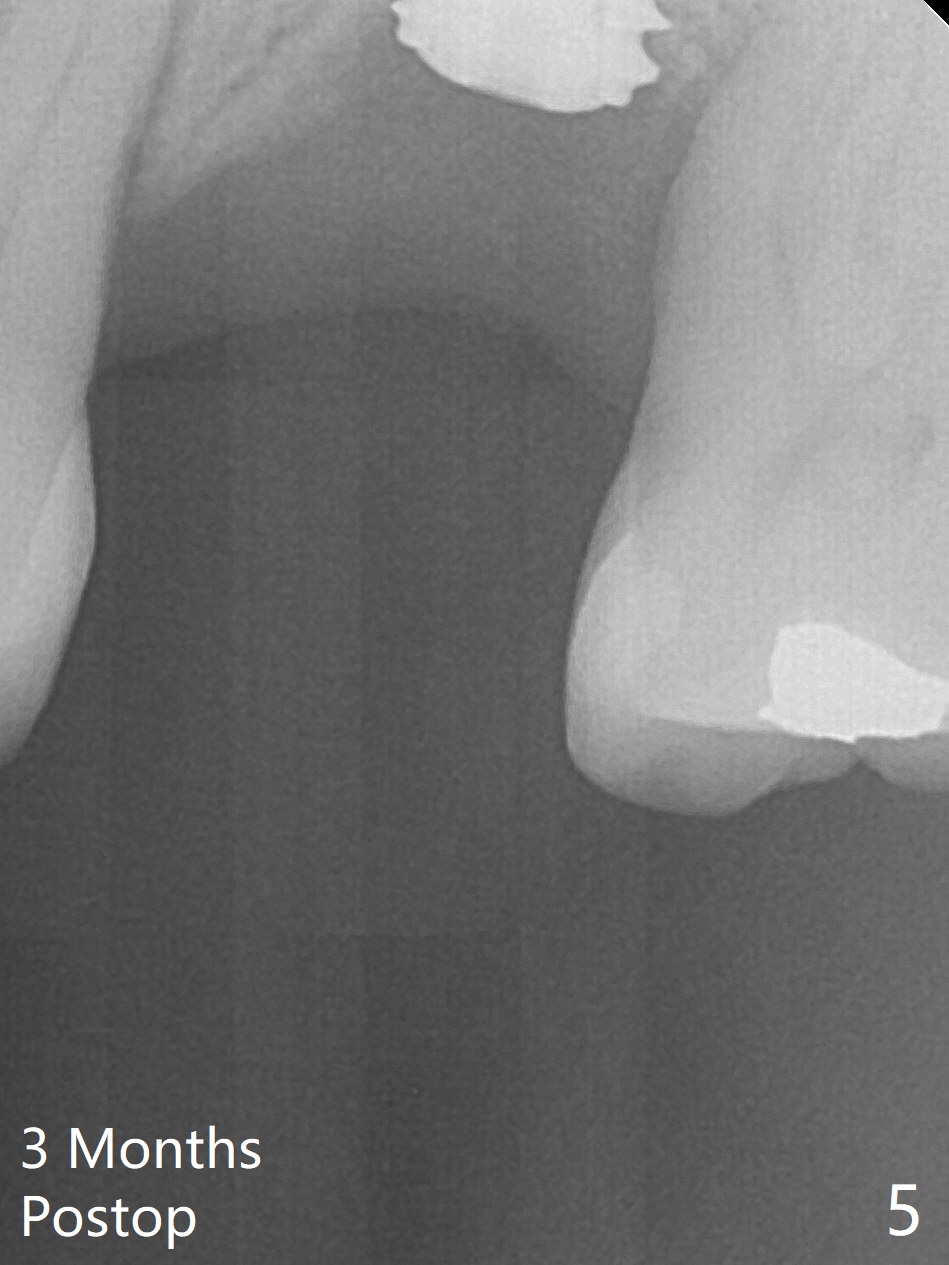

When an IBS implant with PAT surface (4.5x9 mm at #14; Fig.1 CT coronal section with ~ 7 mm bone height) is uncovered nearly 12 months postop, it is loose with a peri-implant space. Immediately post its removal and debridement, an IS dummy implant with SLA surface treatment (Fig.2: 4.5x10 mm) is placed. When a definitive implant is placed (Fig.3,4: 5x7.3 mm), it is subcrestal buccally and nearly equicrestal palatal. The remaining periimplant space is to be filled with demineralized cortical allograft. PAT: photo activated treatment (particles of calcium phosphate and a heating treatment). There is no apparent bone loss 3 months postop (Fig.5,6). The implant is uncovered with placement of a 5.7x4(4) mm cementation abutment and a nonfunctional provisional.